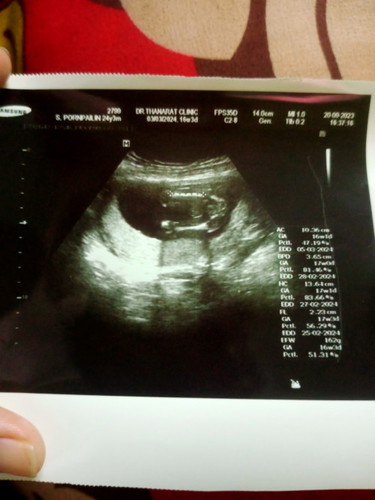

รบกวนแม่ๆช่วยดูหน่อยคะว่าน้องเพศหญิงหรือชาย 💞

เหมือนจะชายเลยค่ะ